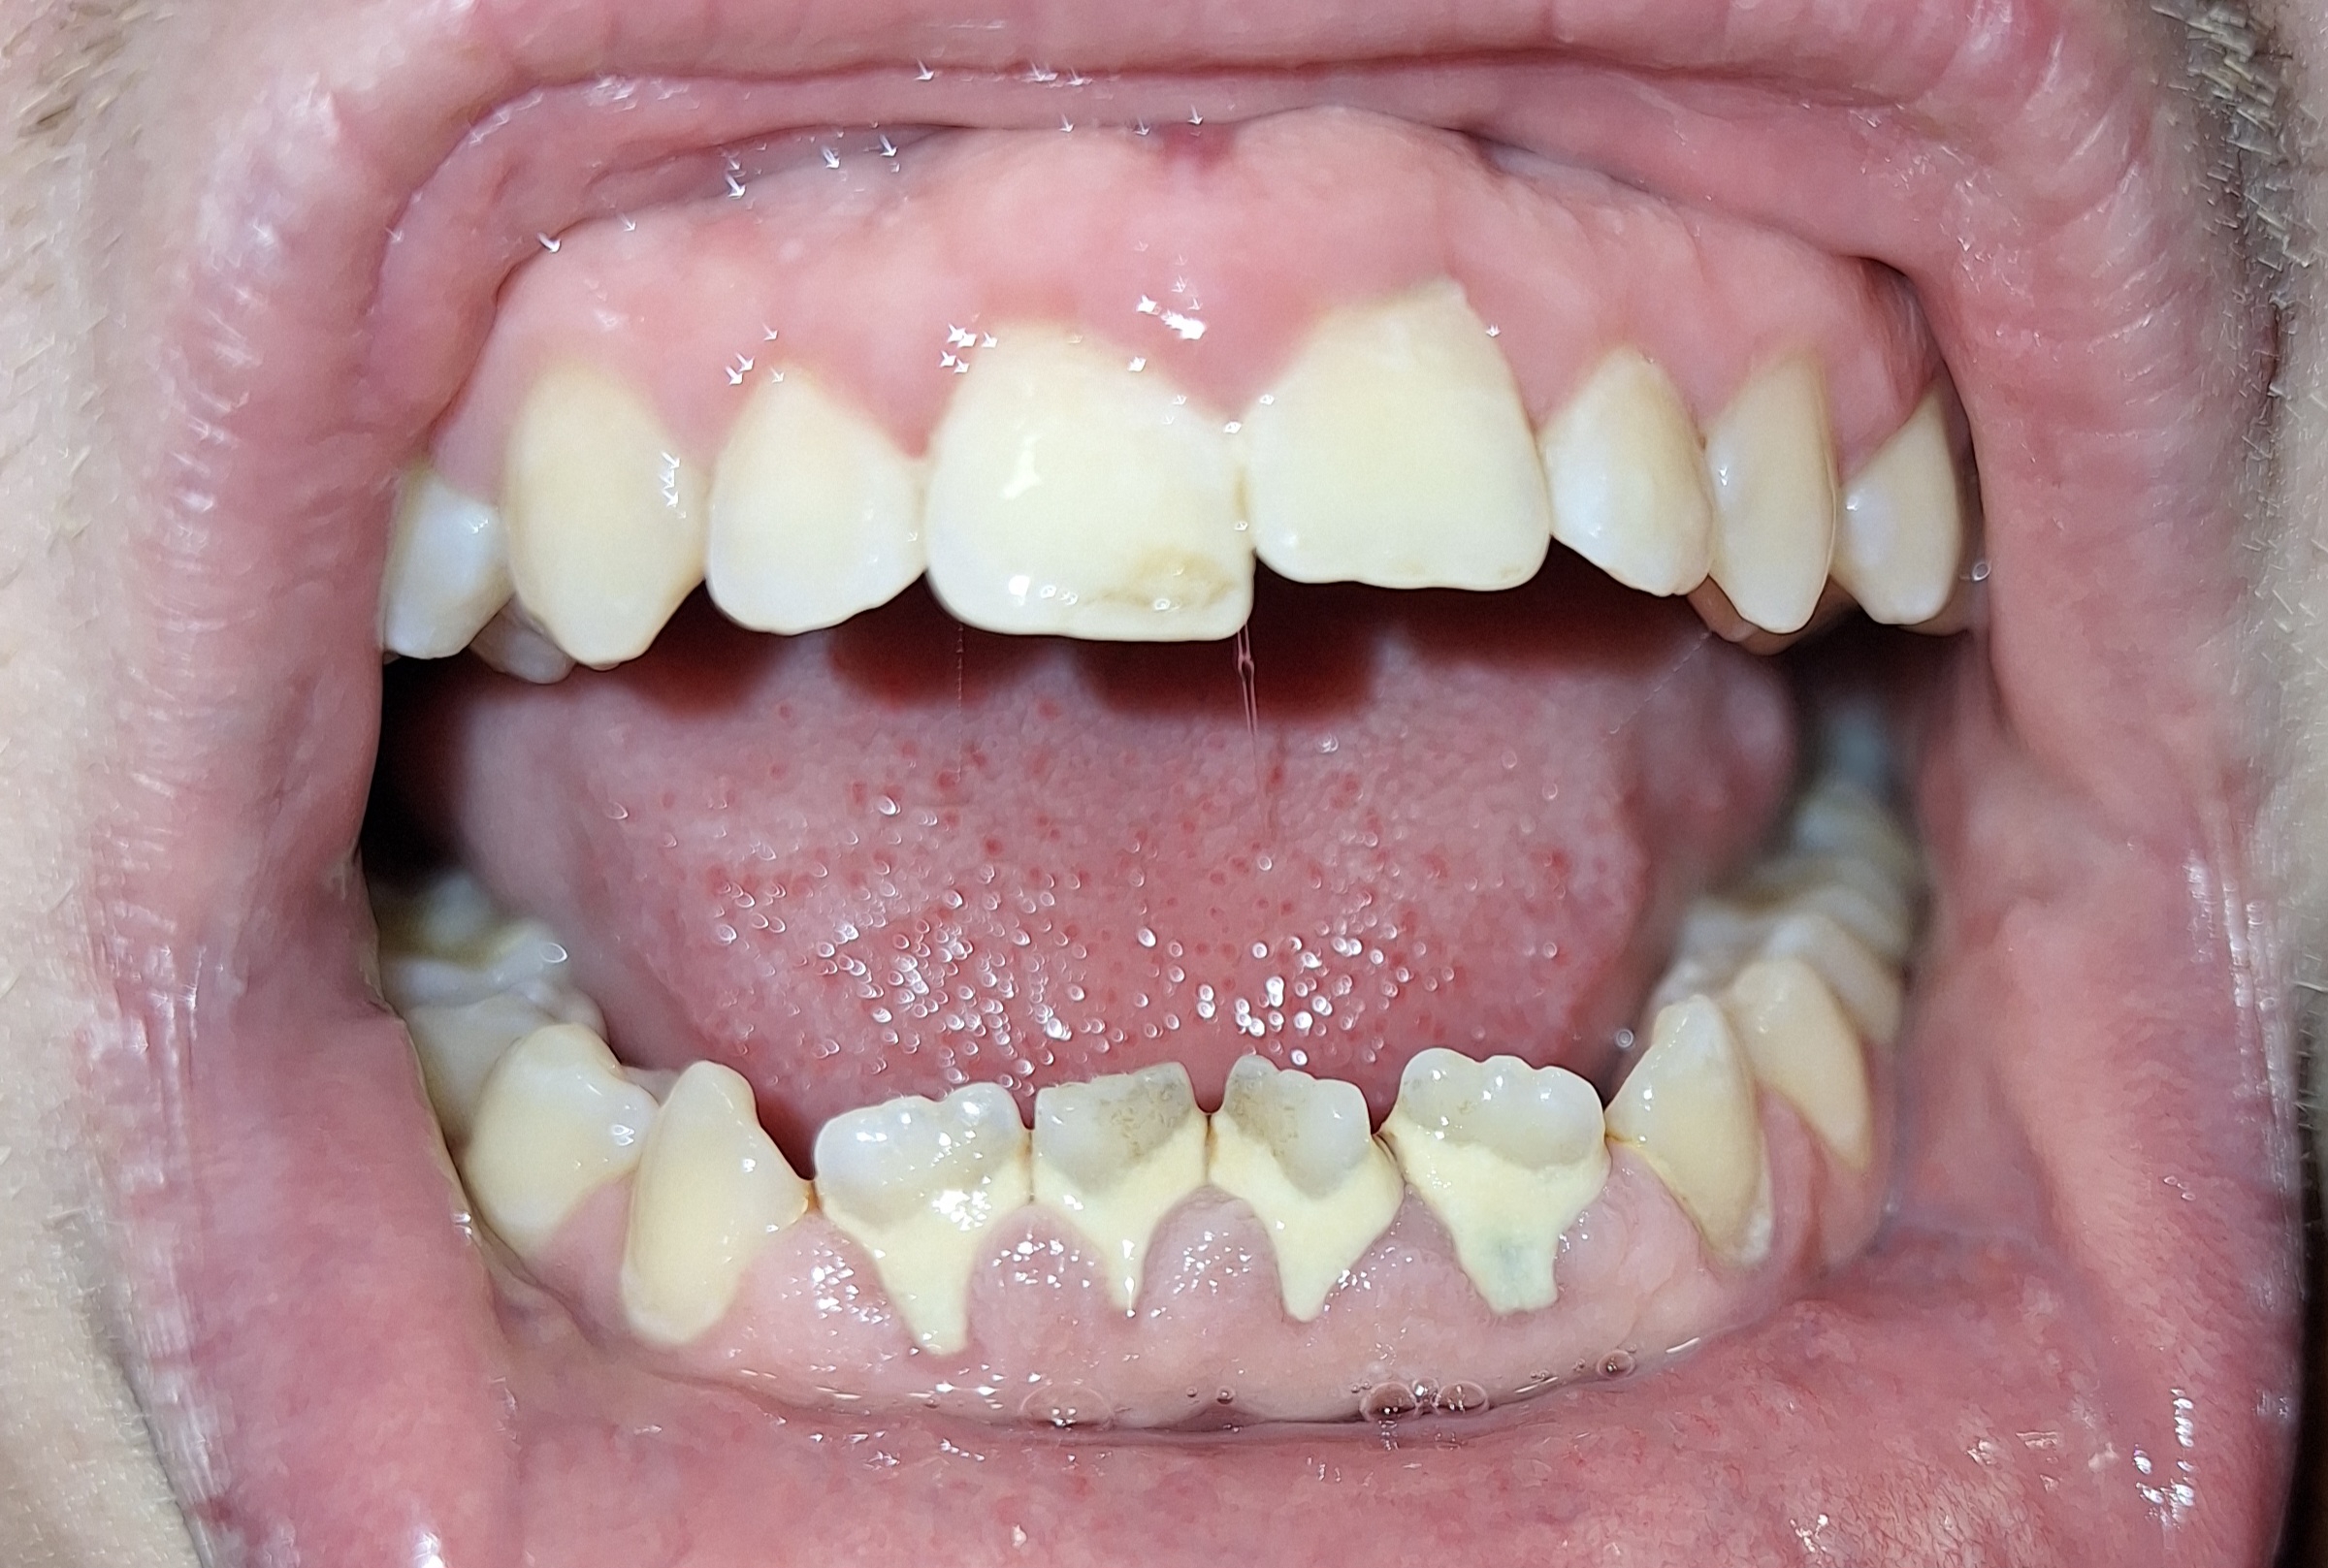

Сап медач.

Опустились дёсны в нескольких местах, обнажились шейки зубов. Чувствительные, болят от прикосновений, могут реагировать на холодное, горячее, сладкое.

Ситуация как примерно на пик2.

Предлагали два варианта:

1) Пластика десны, когда кусок кожи с нёба отрезают и пришивают к десне, чтобы закрыть оголившийся участок

2) Простое заделывание чувствительных мест пломбой/аналогом пломбы без пластики дёсен.

В первом случае меня беспокоит, что будет, если на оголившемся участке зуба есть кариес (сейчас из-за общей более тёмной природной пигментации шеек зубов + налёта не понятно), и я зашью этот кариес под кожу? Кариес будет прогрессировать под десной?

А во втором случае, дохтур сказал, что к заделанным пломбой шейкам зубов десна уже назад не прирастёт, даже если пересадить, то есть пластика дёсен будет невозможна.

ЧТО ДЕЛАТЬ, КАК ЛУЧШЕ ПОСТУПИТЬ?